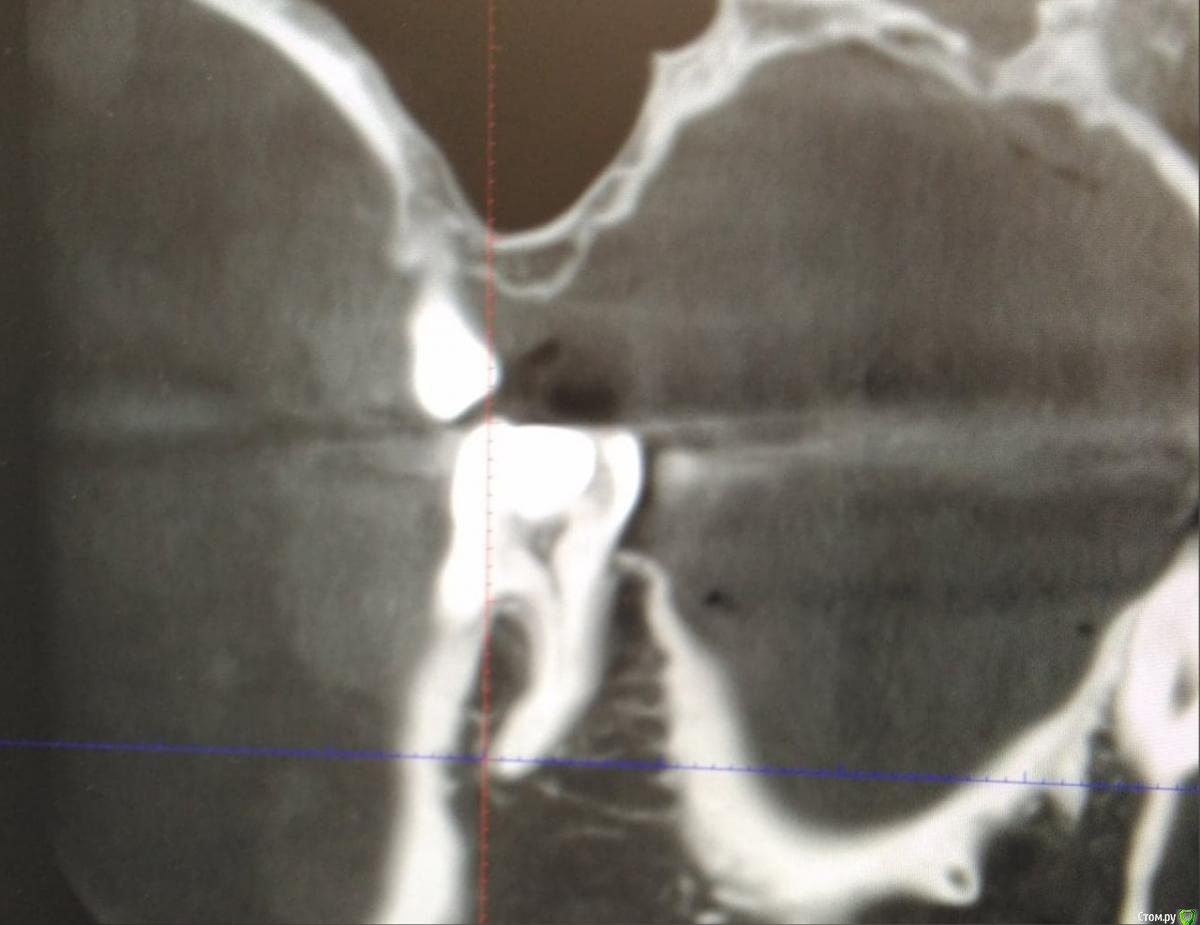

Больше месяца назад мне заменили старую амальгамную пломбу (она была с дефектом и под ней начал развиваться кариес, жевательной поверхности не соответствовала), врач сказала что может немного поболеть, но боль должна пройти, зуб вообще не беспокоил (ни до замены пломбы, ни после). Несколько дней назад начал ныть после полоскания горячей водой. На зубе есть небольшой клиновидный дефект. И уже месяца два как жую только на его стороне, так как другая готовится к протезированию и жевать там нечем.

Что это? Начался пульпит или может быть связано с изменениями во рту?

Фото с амальгамой: